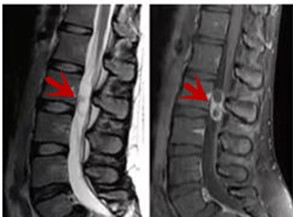

利器三:MRI(核磁共振)

MRI利于磁場和射頻脈沖使體內(nèi)的氫原子核發(fā)生磁共振現(xiàn)象而產(chǎn)生的圖像,對軟組織的分辨率很高,對于脊髓、椎間盤、神經(jīng)、血管、韌帶、骨髓、腰部肌肉及周圍軟組織有很好的顯示效果,可以清晰的顯示腰椎間盤突出對硬膜囊、神經(jīng)根壓迫程度,以及骨折是陳舊還是新鮮,同時在脊髓病變(如脊髓損傷、髓內(nèi)出血或腫瘤)、椎管內(nèi)膿腫/血腫、椎旁肌肉軟組織病變等方面也具有優(yōu)勢,但是檢查時間較長,部分患者可能因體內(nèi)金屬植入物(如心臟起搏器、人工耳蝸等)而無法進(jìn)行檢查。

箭頭提示腰椎管內(nèi)腫瘤